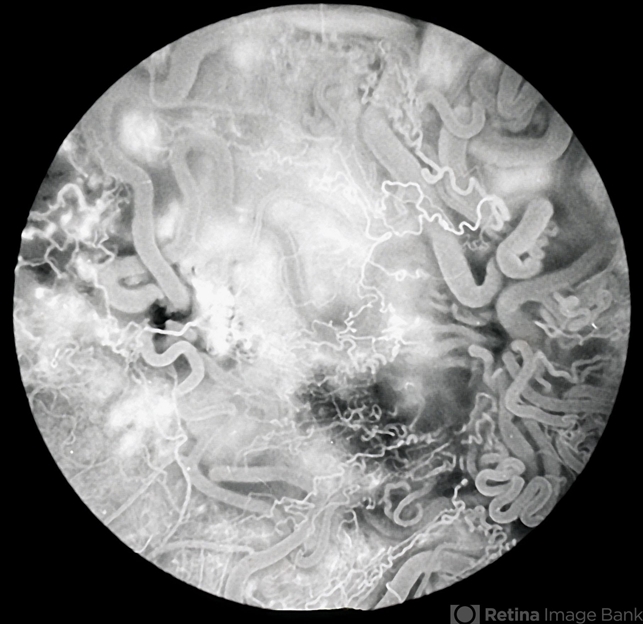

- Retinal AVM

- racemose hemangioma, retinal arteriovenous malformations

- Retinal arteriovenous malformation - Archer group 3 - fluorescein angiogram 4 of 4.